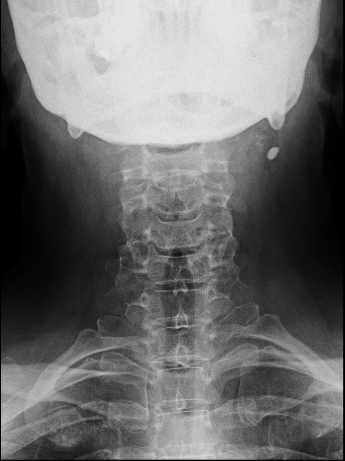

En las imágenes de arriba se aprecian las dificultades anatómicas del abordaje anterior.

RX AP control postoperatoria.

Obsérvese, en la imagen anterior, la incisión usada en relación con la prótesis. No fue necesario realizar ninguna esternotomía (aunque el cirujano torácico estaba avisado). Para mejorar la visión sí que se resecó parte del platillo inferoanterior de Th1.

Difícilmente se aprecia la prótesis

Copia con marcaje de los tornillos de la misma

En las RX lateral de control no se aprecia bien la caja atornillada, sin embargo, la paciente mejoró la clínica álgica y mostró recuperación funcional en MSD en los controles, por lo que decidí esperar a los 6 meses para la RM cervical.